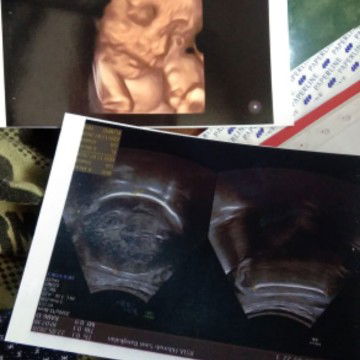

Menantikan saat menjadi ibu

Alhamdulillah launching, baby boy😘😘😘alhamdulillah dgn proses normal dgn bbj 3,8 perjuangan yg sangat luar biasa😌